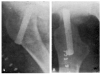

Con buena técnica, todos los resultados son favorables, a pesar de que al cabo de algunos años exista un grado más o menos acentuado de artrosis (véanse la observación núm. 4, fig. 7., A y B, y la observación núm. 9, fig., 8. A, B y C), que corresponden a los dos enfermos que hace más tiempo que están operados, y que en la actualidad aún viven.

Figura 7. A: obs. núm. 4. Enfermo de sesenta y cuatro años, operado en noviembre de 1935. La situación del clavo puede aceptarse como buena (ligeramente craneal). B: obs. núm. 4. Radiografía del mismo enfermo de las dos figuras anteriores, practicada en la actualidad (julio de 1943). Artrosis manifiesta. La cabeza del fémur tiende a aplastarse. Deambulación perfecta.

Figura 8. A: obs. núm. 9. Enferma de cuarenta y cinco años, operada en enero de 1937. El clavo procedía del cadáver de la observación mencionada como fracaso número I, y presentaba unos ligeros depósitos de herrumbre. La situación del clavo es buena. B: obs. núm. 9. El mismo caso de la figura anterior. En proyección lateral también es perfecta la situación del clavo. Éste tuvo que ser extraído a los siete meses de intervenida la fractura, a causa de una persistente supuración. C: obs. núm. 9. Radiografía del caso de las dos figuras anteriores, practicada en julio de 1943. Artrosis muy ligera. El cuello del fémur parece muy estrechado, pero esta deformidad también puede apreciarse en la figura B. Deambulación perfecta.